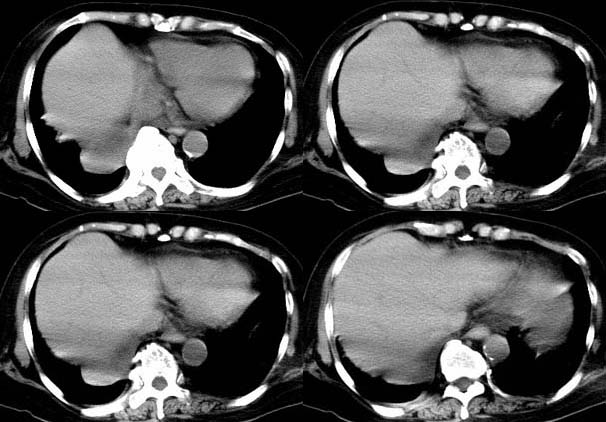

请大家讨论右下肺占位性质。ct值约35-55hu

右下肺癌右肺门淋巴结转移,双肺转移?建议hrct检查。

右下中央型肺癌伴右肺门、纵隔淋巴结转移,双肺肺转移

右下肺癌右肺门淋巴结转移,双肺转移

右下肺中央型肺癌伴阻塞性炎症,并右肺门淋巴结及右肺转移